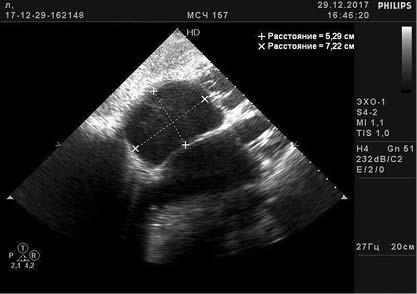

Кроме того, под нашим наблюдением оказался ещё один пациент, которому при скрининговой эхокардиографии был установлен диагноз АЭ. Были обнаружены (рис. 1) удлинение створок ТК, смещение задней и септальной створок к верхушке сердца на 22 мм относительно фиброзного кольца митрального клапана, расширение фиброзного кольца ТК, увеличение объёма правого предсердия (5,29×7,22 см), уменьшение размеров ПЖ, стенки ПЖ утолщены до 4 мм, в верхней трети межжелудочковой перегородки — прерывание эхо-сигнала до 4 мм со сбросом крови слева направо при цветовом допплеровском картировании (рис. 2). Систолическое давление легочной артерии 46 мм рт.ст. Фракция выброса (Симпсон) 36%. Уровень N-концевого пропептида мозгового натрийуретического гормона на момент обращения 650 пг/мл (референсное значение до 150 пг/мл).

Рис. 1. Данные эхокардиографии: атриализированная часть правого желудочка, уменьшение его размеров, расширение фиброзного кольца трёхстворчатого клапана